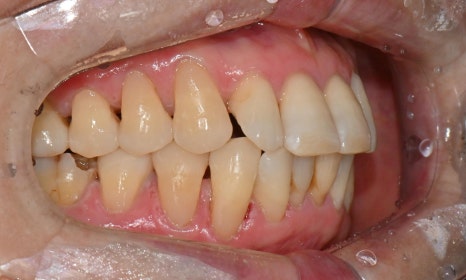

본 환자는 70세 여환으로 가만히 입을 다물고 있을 때 화난 것 처럼 보인다고 해서 튀어나온 앞니를 조금 넣고 싶다는 주소로 내원하셨습니다. 전체적인 치아 및 잇몸 상태를 검진해본 결과, 마모되어 깨진 치아도 있었고, 치경부(치아와 잇몸 사이 경계 부위)가 마모되어 파여 있는 부위도 많았습니다.

2025.2.3. 초진